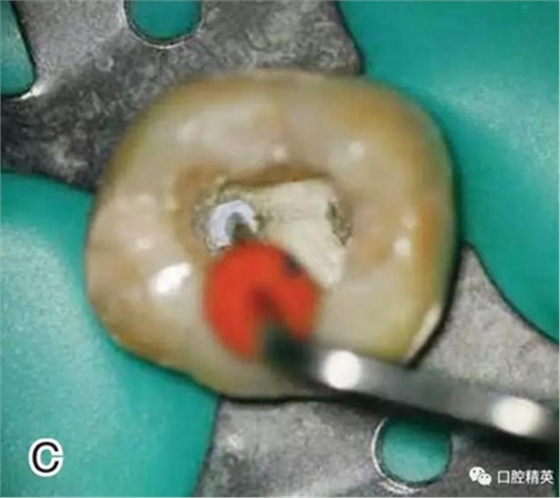

5、去除根管口外牙膠尖

調(diào)節(jié)好攜熱器的工作溫度,將攜熱器工作尖放置在根管口,啟動加熱源,去除根管口外多余的牙膠尖部分,用大號的垂直加壓器在根管口向根方輕輕加壓(圖5)。

圖5 去除根管口外牙膠尖,A、B.?dāng)y熱器尖去除根管口處的牙膠尖

C、D.大號垂直加壓器輕輕加壓